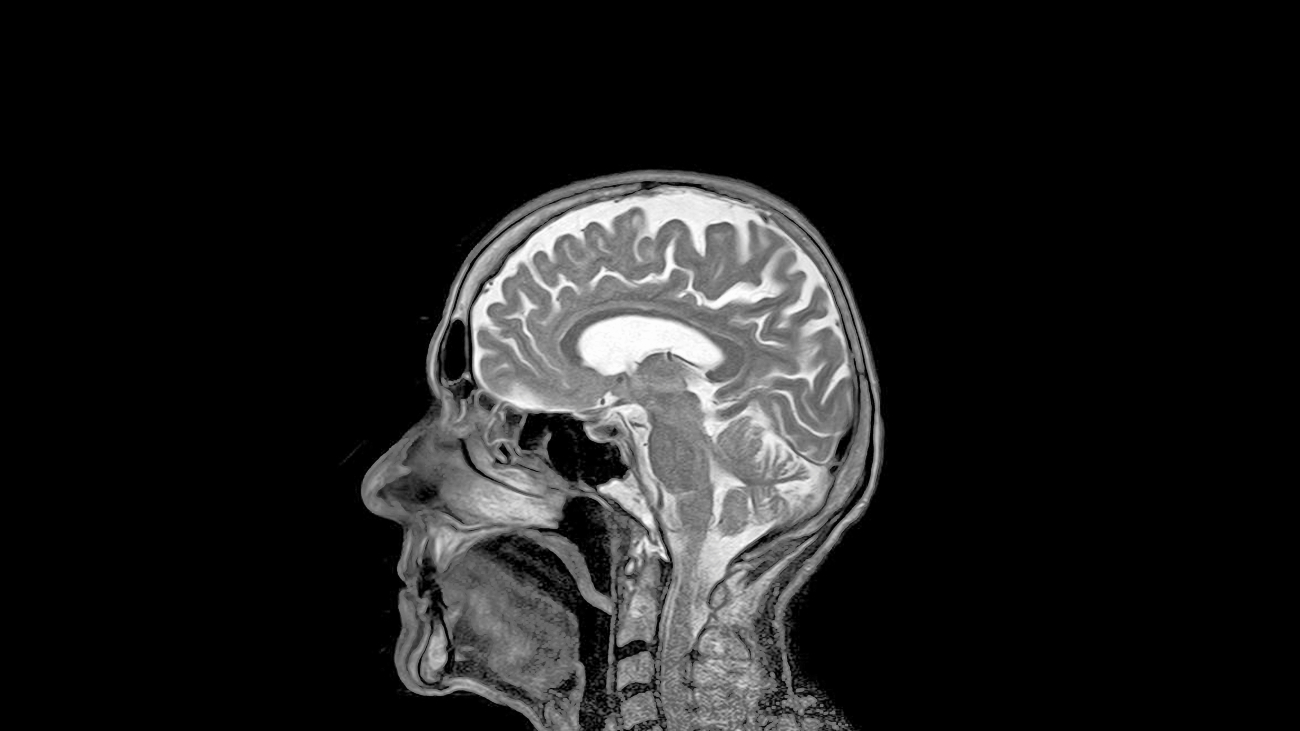

Hersenschudding MRI-scan

Na een val of een klap tegen het hoofd kan de normale werking van de hersenen tijdelijk verstoord zijn. Soms verlies je zelfs korte tijd je bewustzijn. Maar wat gaat er bij een hersenschudding precies mis?